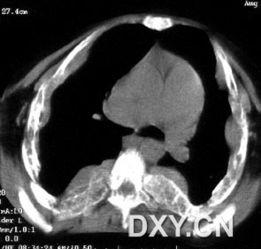

4. 心脏变化:长期贫血症可能导致心脏增大,出现心脏杂音等症状。